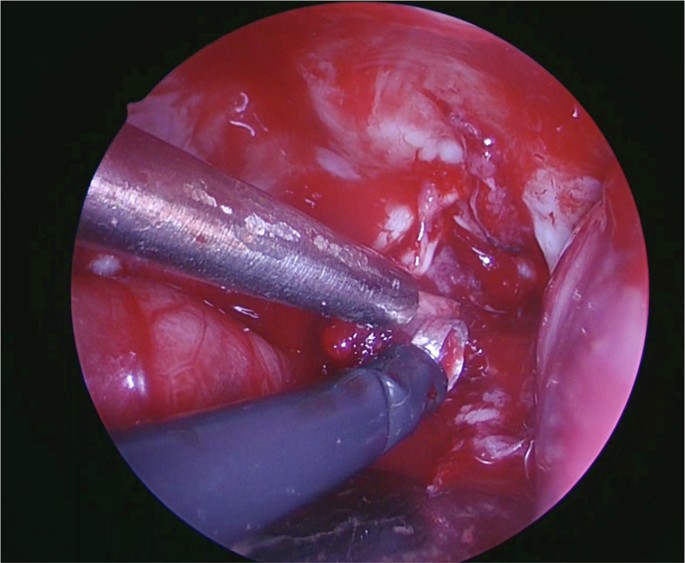

The curette end-effector, shown in Fig. 5, demonstrated the highest overall performance across all approaches, It performed the best, consistently, in the subfrontal approach and its poorest performance was in the second animal during the transparietal approach (Fig. 3). It was considered very easy when manipulating nerves during the subfrontal approach, very easy in the first animal and easy in the second animal of the transparietal approach, and was predominantly deemed very easy to manipulate cerebellar tissue. The forces applied were described as “appropriate and correct”, and the instrument “very easy and precise”.